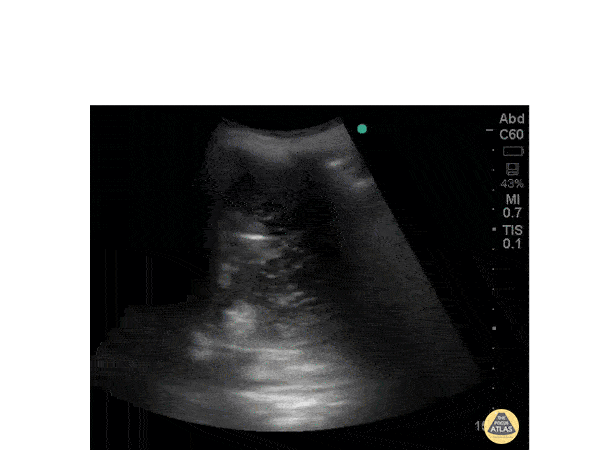

Pulmonary - Pleural Effusion

Patient of chronic renal failure with signs of fluid overload and bilateral pleural effusion on chest radiograph.POCUS ---Echogenic material within the fluid. Echogenic material seen within the fluid- Suggestive of Exudative pleural effusion. Transudative pleural effusion will be non echogenic. Dr. Ramachadran